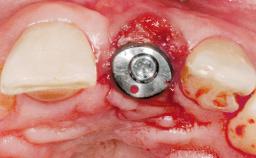

Bone Augmentation Horizontal|Simultaneous

Augmentation Materials Autogenous chips|Membrane

Placement Protocol Immediate implant placement

Socket Integrity Sufficient, with intact bone walls

Bone Volume Sufficient, with intact walls